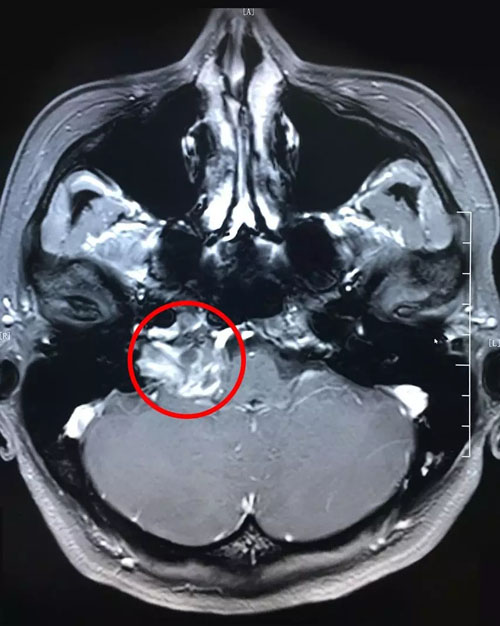

從最新的影像資料上來(lái)看,患者右側(cè)橋小腦區(qū)占位、頸深部占位,神經(jīng)鞘瘤的可能性很大。

患者術(shù)前影像:右側(cè)橋小腦區(qū)占位,頸深部占位

仔細(xì)閱讀了患者的影像資料,憑借著多年豐富的臨床經(jīng)驗(yàn),沈教授判定患者的病變是頸靜脈孔區(qū)神經(jīng)鞘瘤漫延侵犯到橋小腦部位。頸靜脈孔區(qū)神經(jīng)鞘瘤是一種非常罕見(jiàn)的腫瘤,臨床上很少見(jiàn)。為嚴(yán)謹(jǐn)籌備手術(shù),沈教授組織科室專家,并邀請(qǐng)腦電監(jiān)測(cè)專家進(jìn)行了會(huì)診。